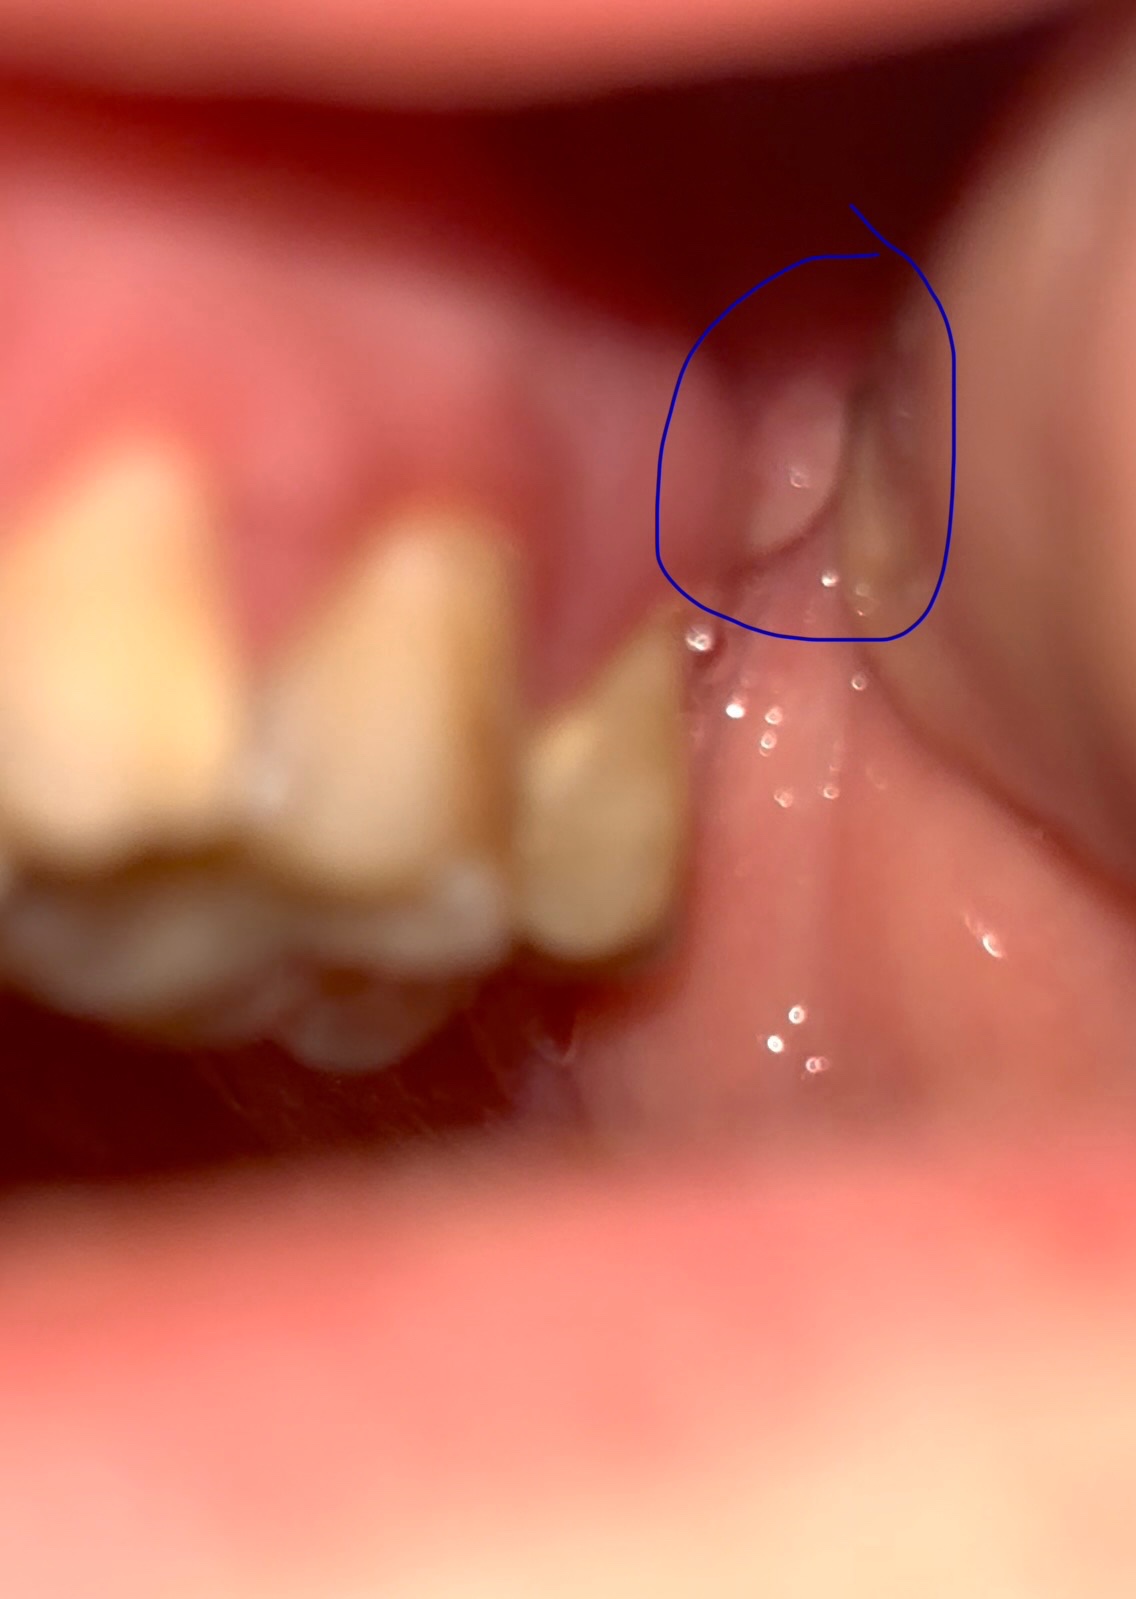

Добрый, день беспокоит такая проблема вот уже 3 день как на верхней челюсти на десне с лева между 7 зубом и там где должен быть 8 зуб. Но его у меня нету с лева еще не вылез а вот с права есть. В сентябре лечил зубы 5 и 6 делали кт верхней челюсти врач говорил что повезло что зубы мудрости ровно растут. Вообщем касательно симптомов то есть такое как не чувство давление а больше точечная боль, когда задеваю то место щекой или если левую часть лица напрягаю. По внешнему виду, оно что ли белое и свисает. А на ощуп выпуклость что ли.